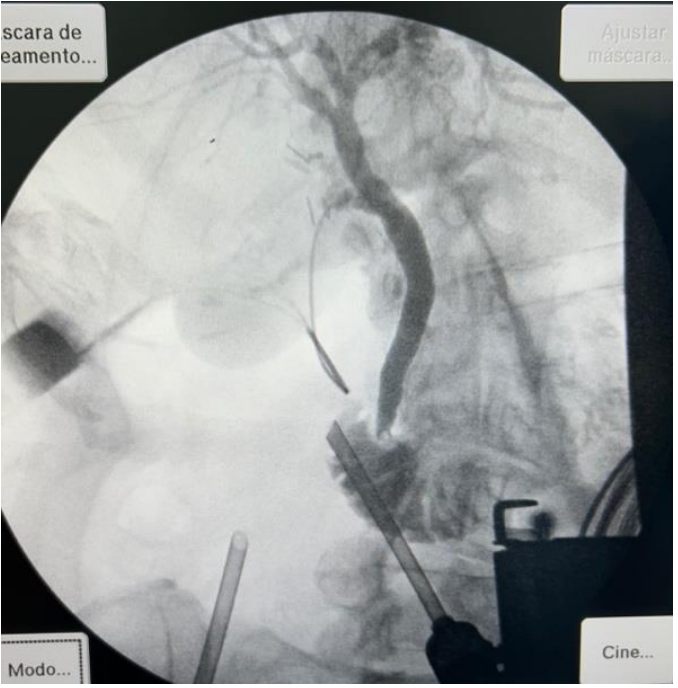

Foi submetida à colecistectomia videolaparoscópica e optou-se por realizar uma colangiografia intraoperatória que resultou na imagem a seguir.

Assinale a alternativa que corresponde ao diagnóstico encontrado: